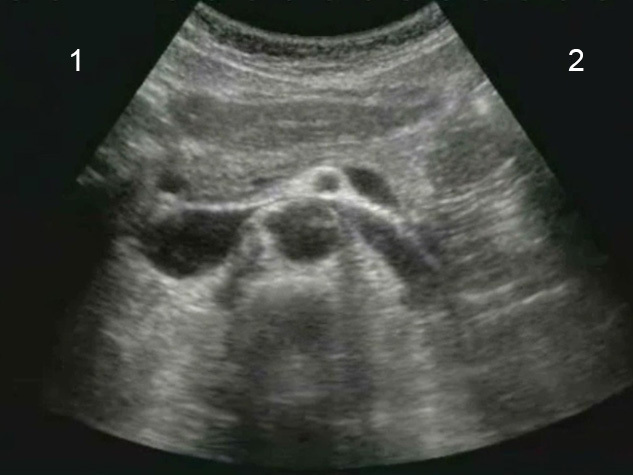

主动脉横切探头方向图

患者右侧

患者左侧